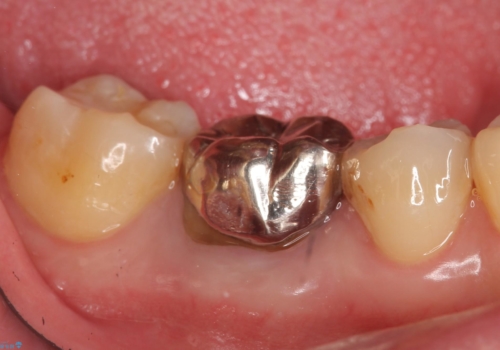

- 右下の奥歯の鈍い痛みがずっと続いているので診て欲しいといらっしゃった方の症例です。

検査の結果右下6に根尖病変を認めたため、再根管治療を行いました。

その後症状の消失を確認し、オールセラミッククラウンによる補綴を行いました。